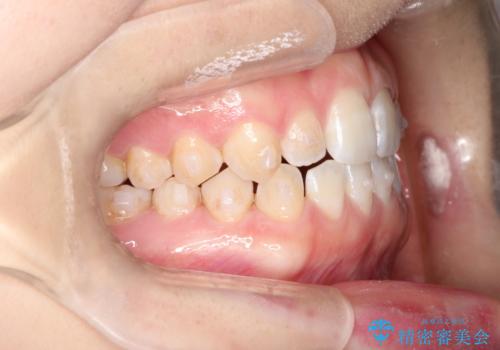

前歯の隙間を閉じたい インビザラインによる矯正

- 上下の前歯に隙間があるとのことで来院されました。

インビザラインにて隙間を閉じる矯正を行いました。